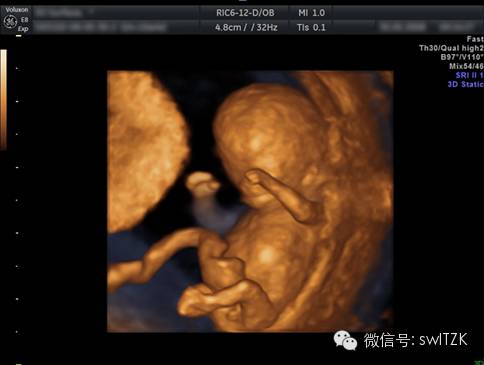

四月妊娠,可以看到一个大致成形的胎儿,刚刚分化出来的四肢。

这也是四月妊娠的时候,可以看到胎儿在宫腔内的形态,四肢已经基本分化完成,颜面部虽然尚不清晰,但已经能基本看到轮廓了。